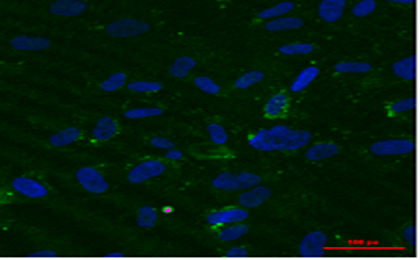

Alkahoittrong lá đu đủ đã được chứng minh có hoạt tính gây độc với một số dòng tế bào ung thư đã thử nghiệm như ung thư phổi, ung thư vú, ung thư máu và ung thư biểu mô. Vì vậy, PGS.TS Đỗ Thị Hoa Viên và cộng sự đã đề xuất phương pháp sản xuất hỗn hợp alkaloit chọn lọc với hiệu suất cao tới 0,2% có thể ứng dụng trong sản xuất quy mô công nghiệp.